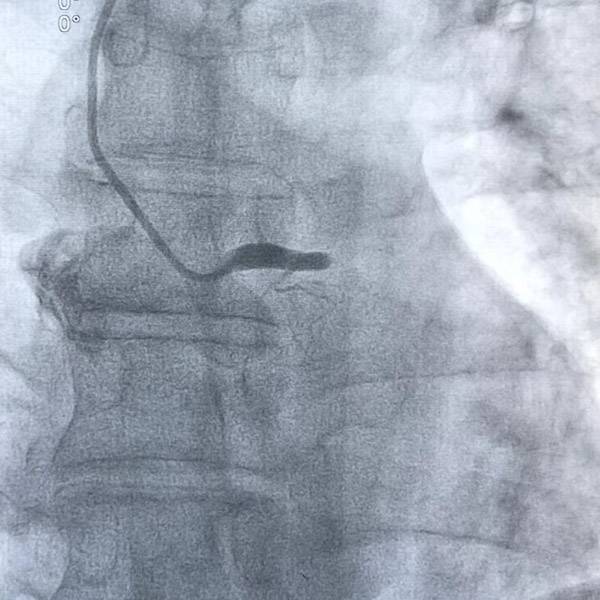

周先生順利被送入介入室,不到10分鐘就做完了心臟造影,結(jié)果令人驚愕——“左主干中遠(yuǎn)端100%閉塞”!

陶林仔細(xì)分析了患者的病情后,當(dāng)機(jī)立斷為患者進(jìn)行手術(shù),一場(chǎng)爭(zhēng)分奪秒的搶奪戰(zhàn)就此拉開序幕。介入團(tuán)隊(duì)憑借豐富的臨床經(jīng)驗(yàn),第一時(shí)間就找到了患者的左主干開口,如線穿針般細(xì)心地將導(dǎo)絲穿過病變血管,球囊擴(kuò)張后成功植入支架及時(shí)疏通血管,左主干狹窄解除,血流恢復(fù),整個(gè)過程不到一個(gè)小時(shí),成功地將患者從死亡線上拉了回來。